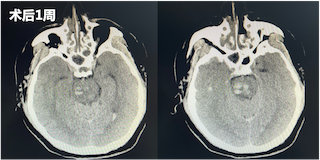

术后一周再次复查CT显示脑干中的血肿明显较前减少。直至三周后,再次复查CT,患者已经没有血肿块,意识较前明显好转,遂转入普通病房继续治疗。在普通病房,患者还同时接受专业的康复训练和中医针灸治疗,患者四肢活动较前好转,目前,已出院至康复医院继续进行康复训练。